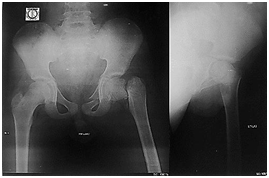

Excellent union was achieved within 3 months (Figure 2-5).

Figure 5 After removal of Ilizarov fixation, good union is achieved.